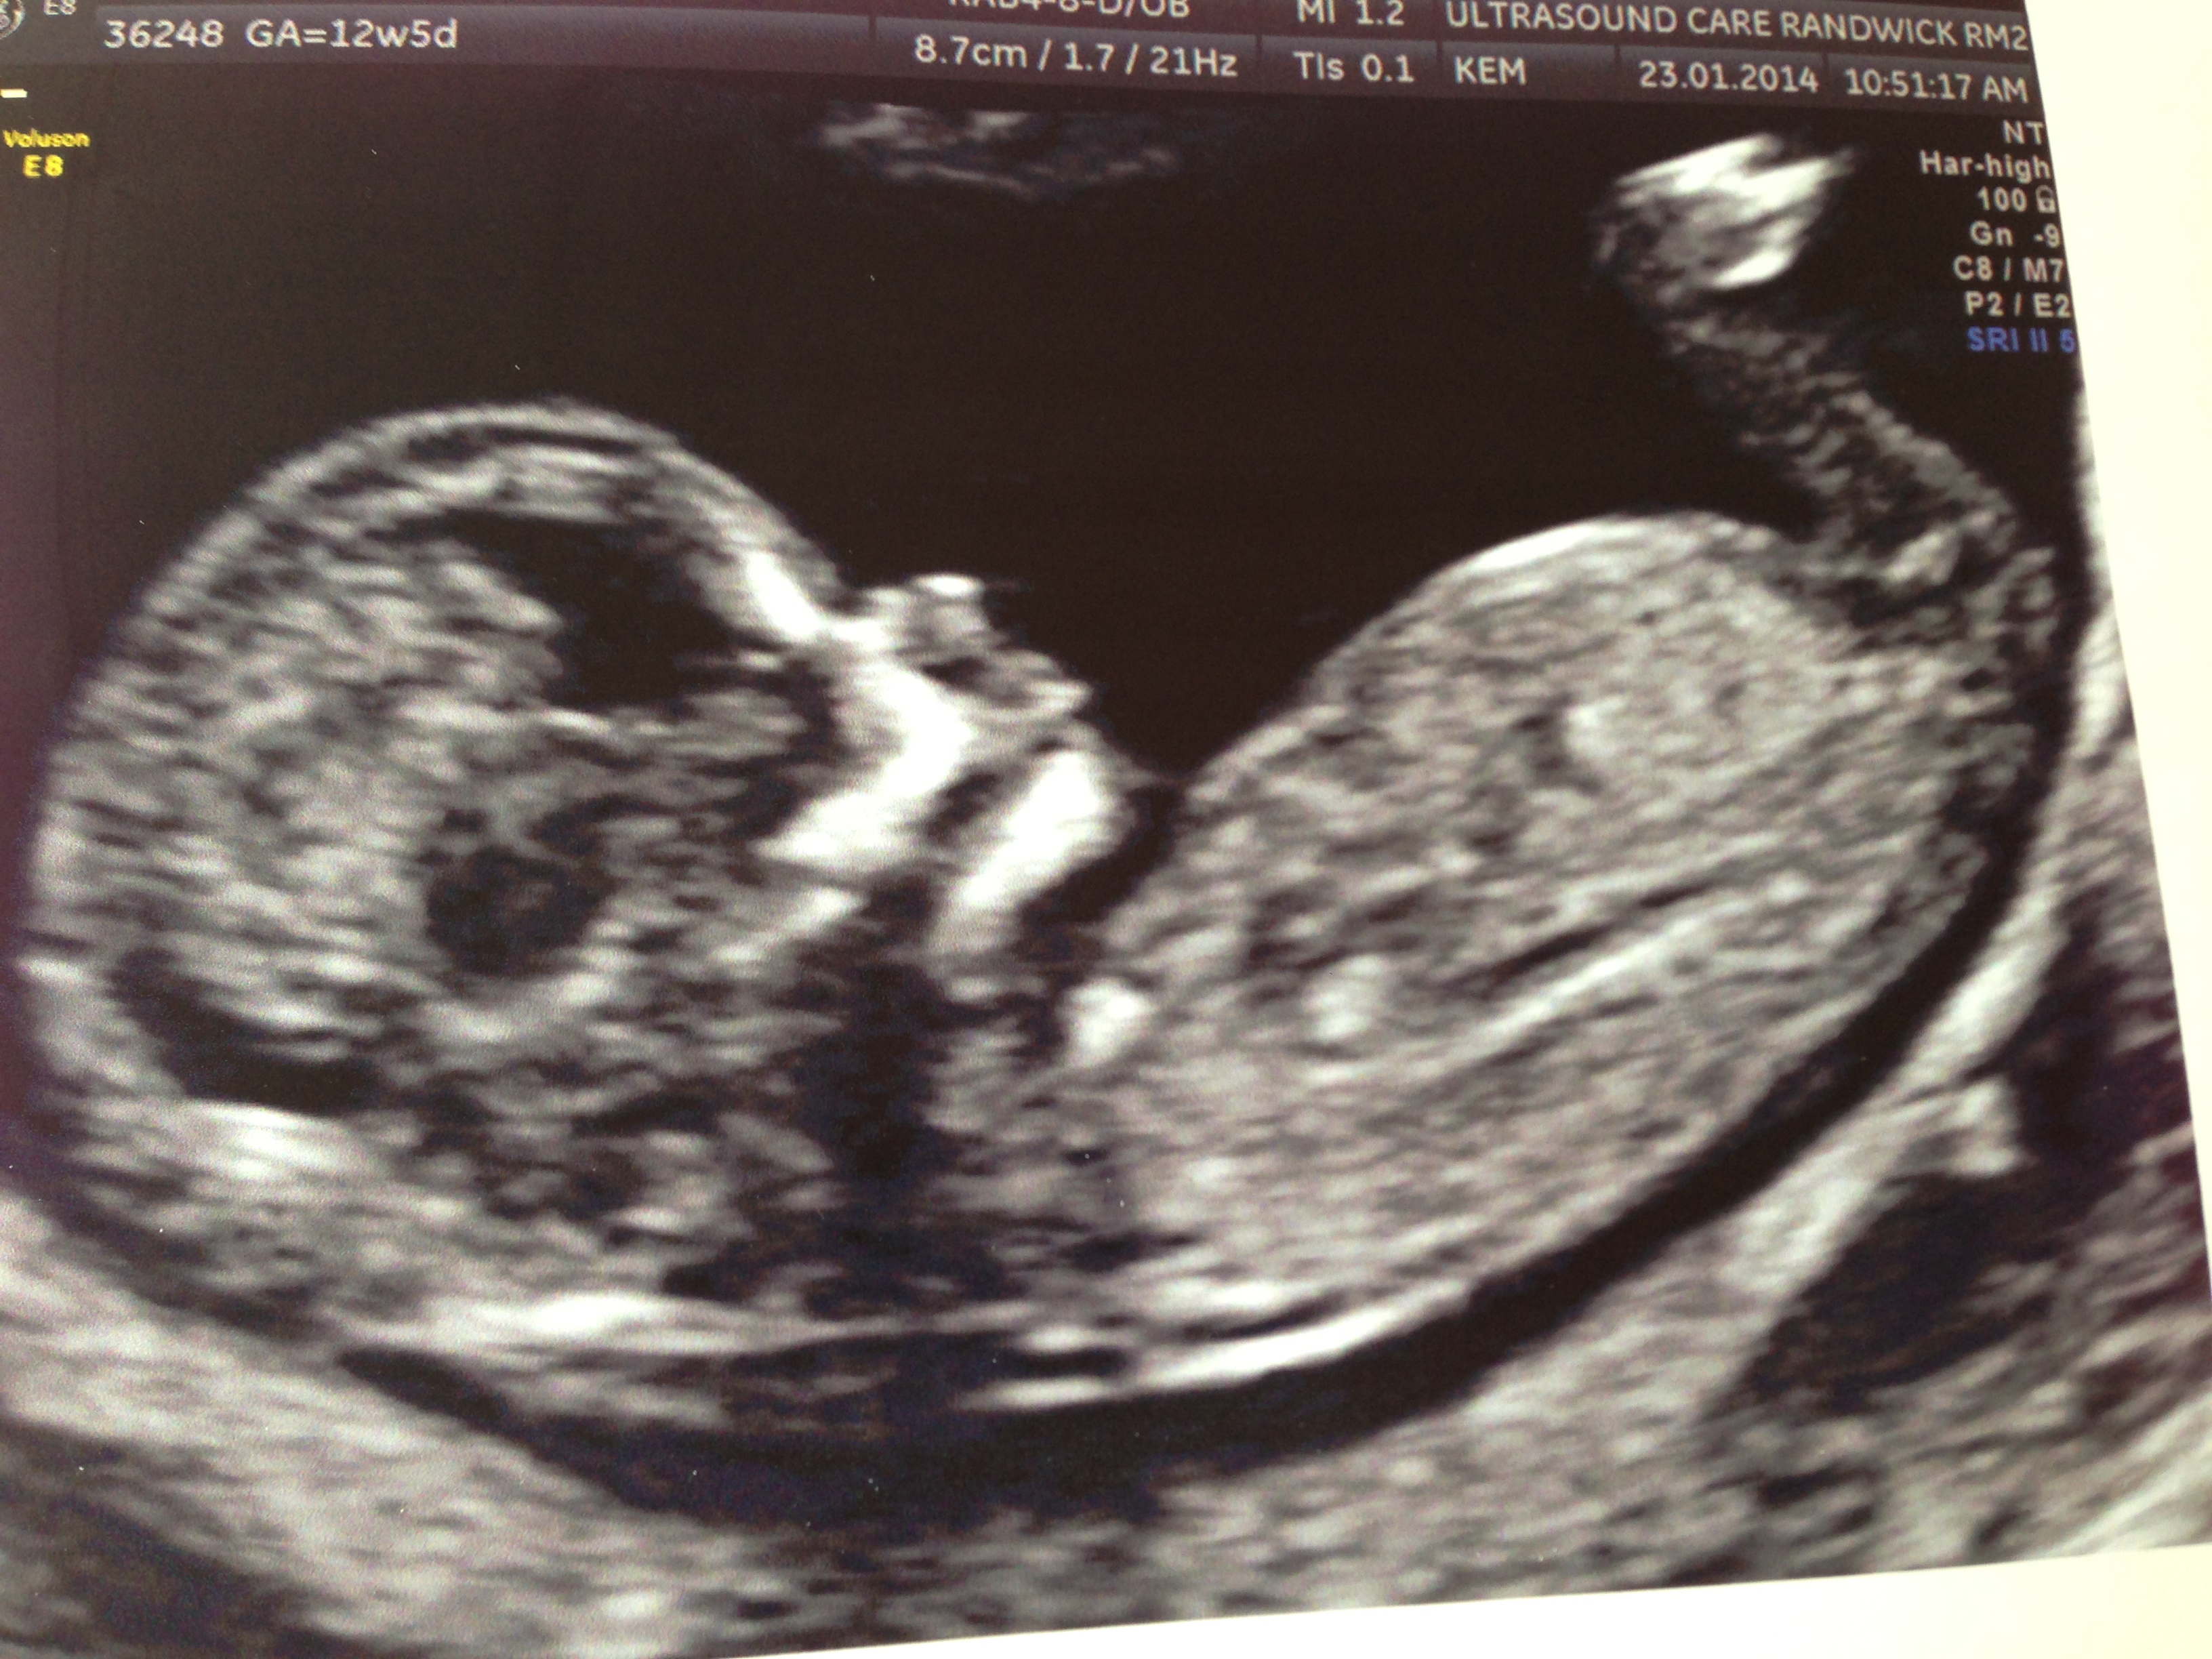

My name is Vera, and I'm very curious as to whether I'm having a boy or girl. Please take a guess nub experts, it would be greatly appreciated! Thank you!

sorry, baby is 12weeks and 5 days!

think blue

I am thinking girl by the skull i ould be wrong it's just an opinion good luck hope you get what you are wanting.